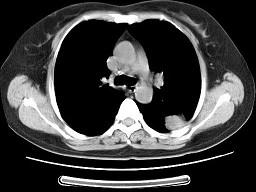

问题 女,52岁,左侧背痛一月,胸部CT如图,最可能的诊断为 ( )

选项 A、左肺炎性假瘤 B、肺隔离征 C、左肺周围型肺癌 D、左肺感染 E、左肺中央型肺癌

答案 A